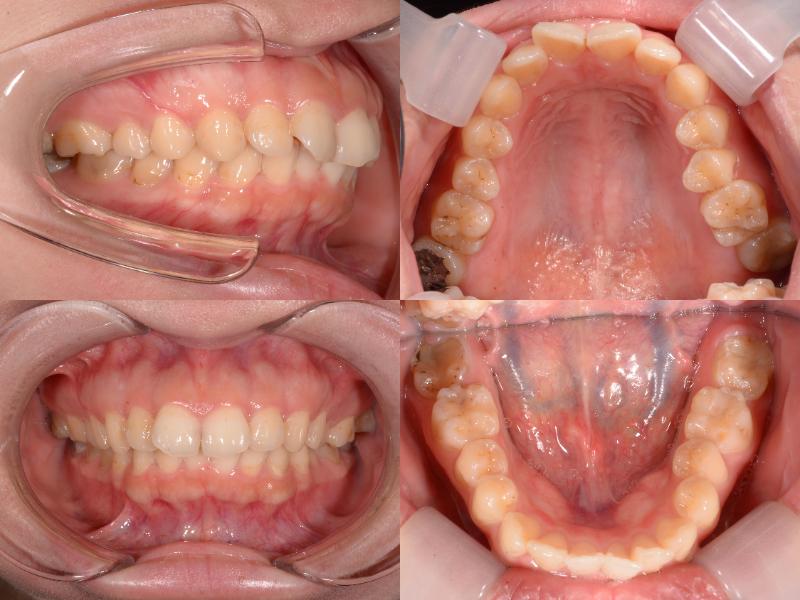

治療の結果、口元の突出感とディープバイトの改善が認められ、より自然で調和のとれた横顔を得ることができました。

ディープバイトの小臼歯抜歯症例では、噛み合わせがより深くなるリスクがあります。

この症例では、上顎前歯唇側にアンカースクリューを2本埋入し、上顎前歯の圧下を行うことでリスクをコントロールしました。

また、根尖性歯周炎を伴う歯への力の負担を最小限にするよう配慮しています。